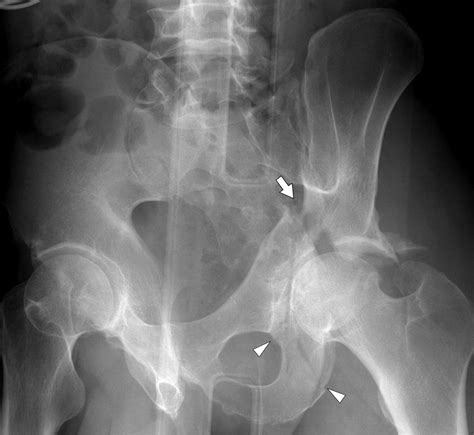

Transverse Horizontal fracture line across the acetabulum

Diagnosis of Fractures of the Acetabulum

Diagnosing fractures of the acetabulum involves a combination of clinical examination and imaging studies. The diagnostic process typically includes:

• X-rays: Initial imaging to visualize the fracture pattern and assess the extent of the injury.